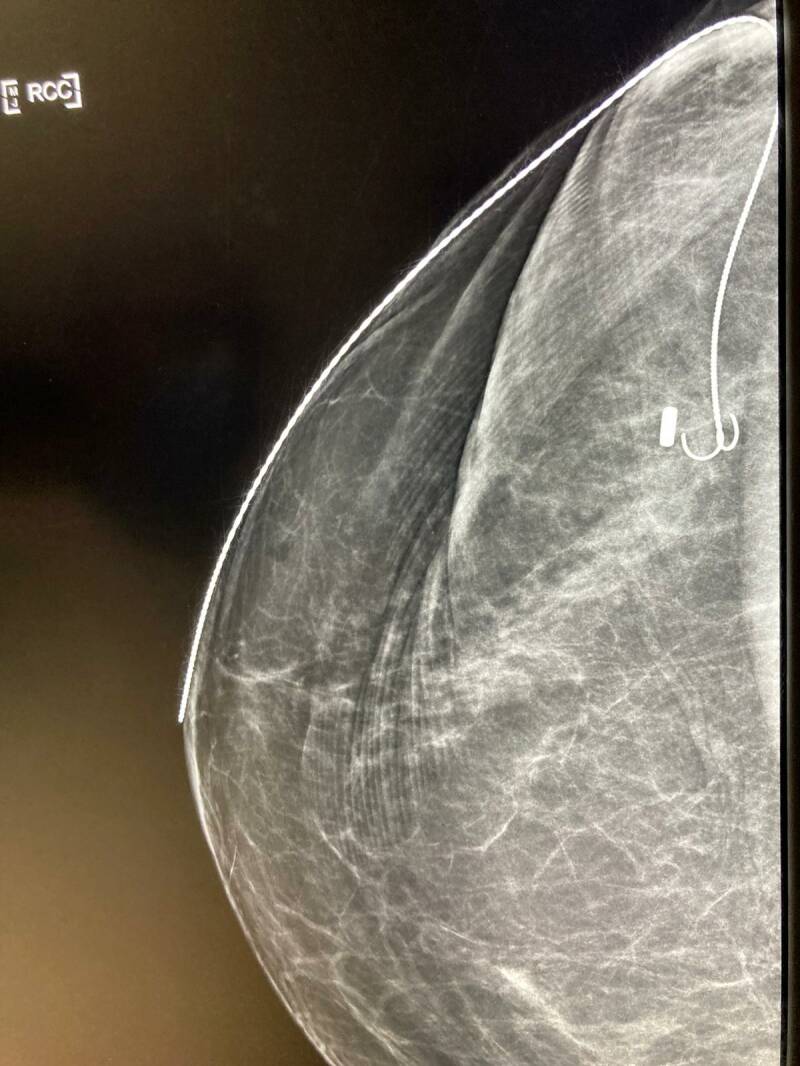

De dag begon met het aanbrengen van de tweede marker: de draad.

Dat ging niet helemaal lekker en moest opnieuw, maar zat volgens de deskundigen perfect op z'n plek. De foto's zijn gemaakt met de mammografie: Arvid " zag er niet heeel charmant uit, zo tussen de tosti-ijzers"

Op mijn borst met dikke stift de plek van de kanker en de diepte:2,5 cm.

Vervolgens pleisters om het uiteinde van de draad vast te pakken en om te voorkomen dat er stift op de mammografie-machine kwam. Owhja, en een mitella om mijn arm stil te houden en te voorkomen dat ik de draad zou verplaatsen met een beweging

Hier een foto van de mammografie waar de marker duidelijk zichtbaar is. De kanker zit er rechts naast.